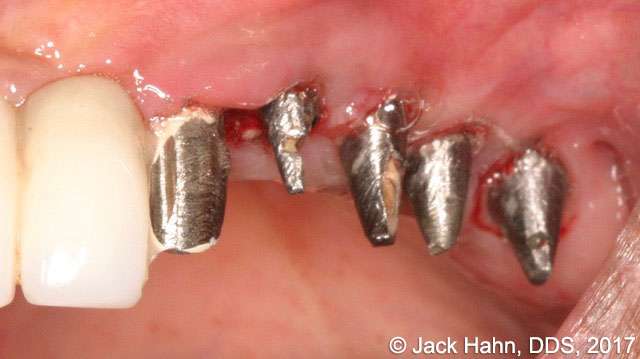

CASE #6 Laser Crown Lengthening

Dr. Hahn performed crown lengthening on old Sterioss implants that he placed over 25 years ago. The photos show the surgical site before the crown lengthening, immediately following the crown lengthening, and 30 days postoperatively. Dr. Hahn notes the excellent healing in the post-op visit.